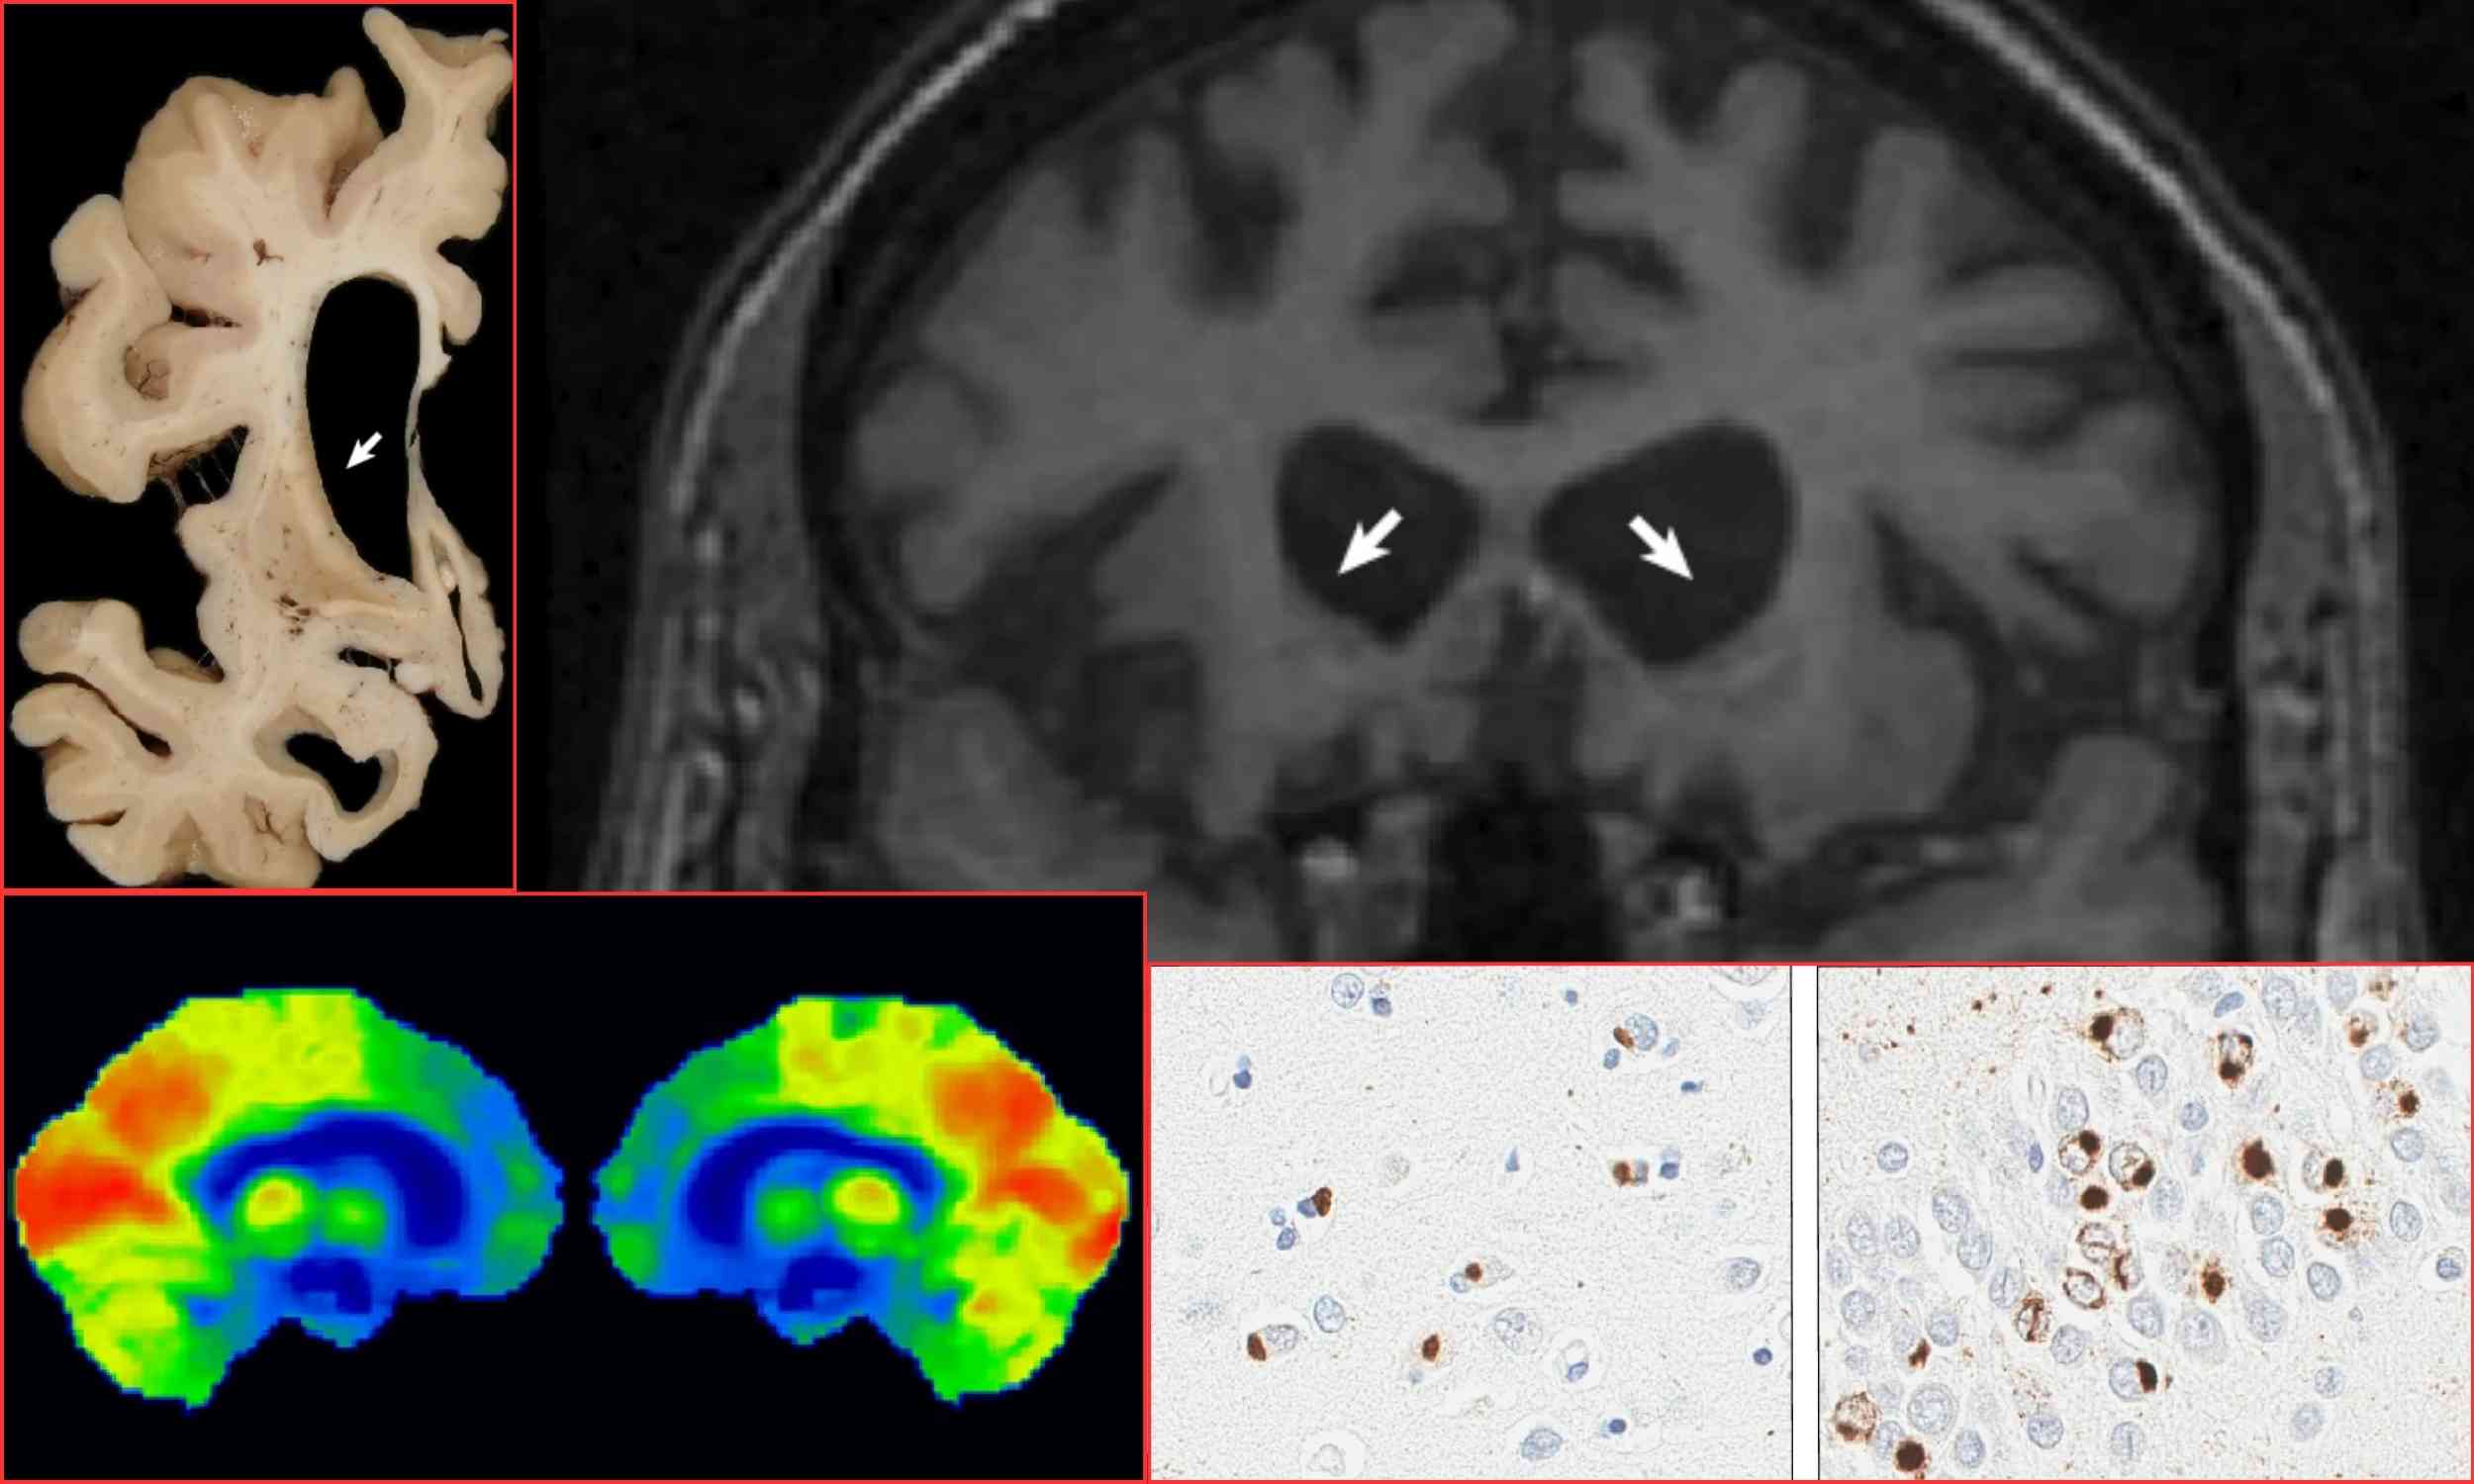

Blood test developed to detect Alzheimer's is now ...